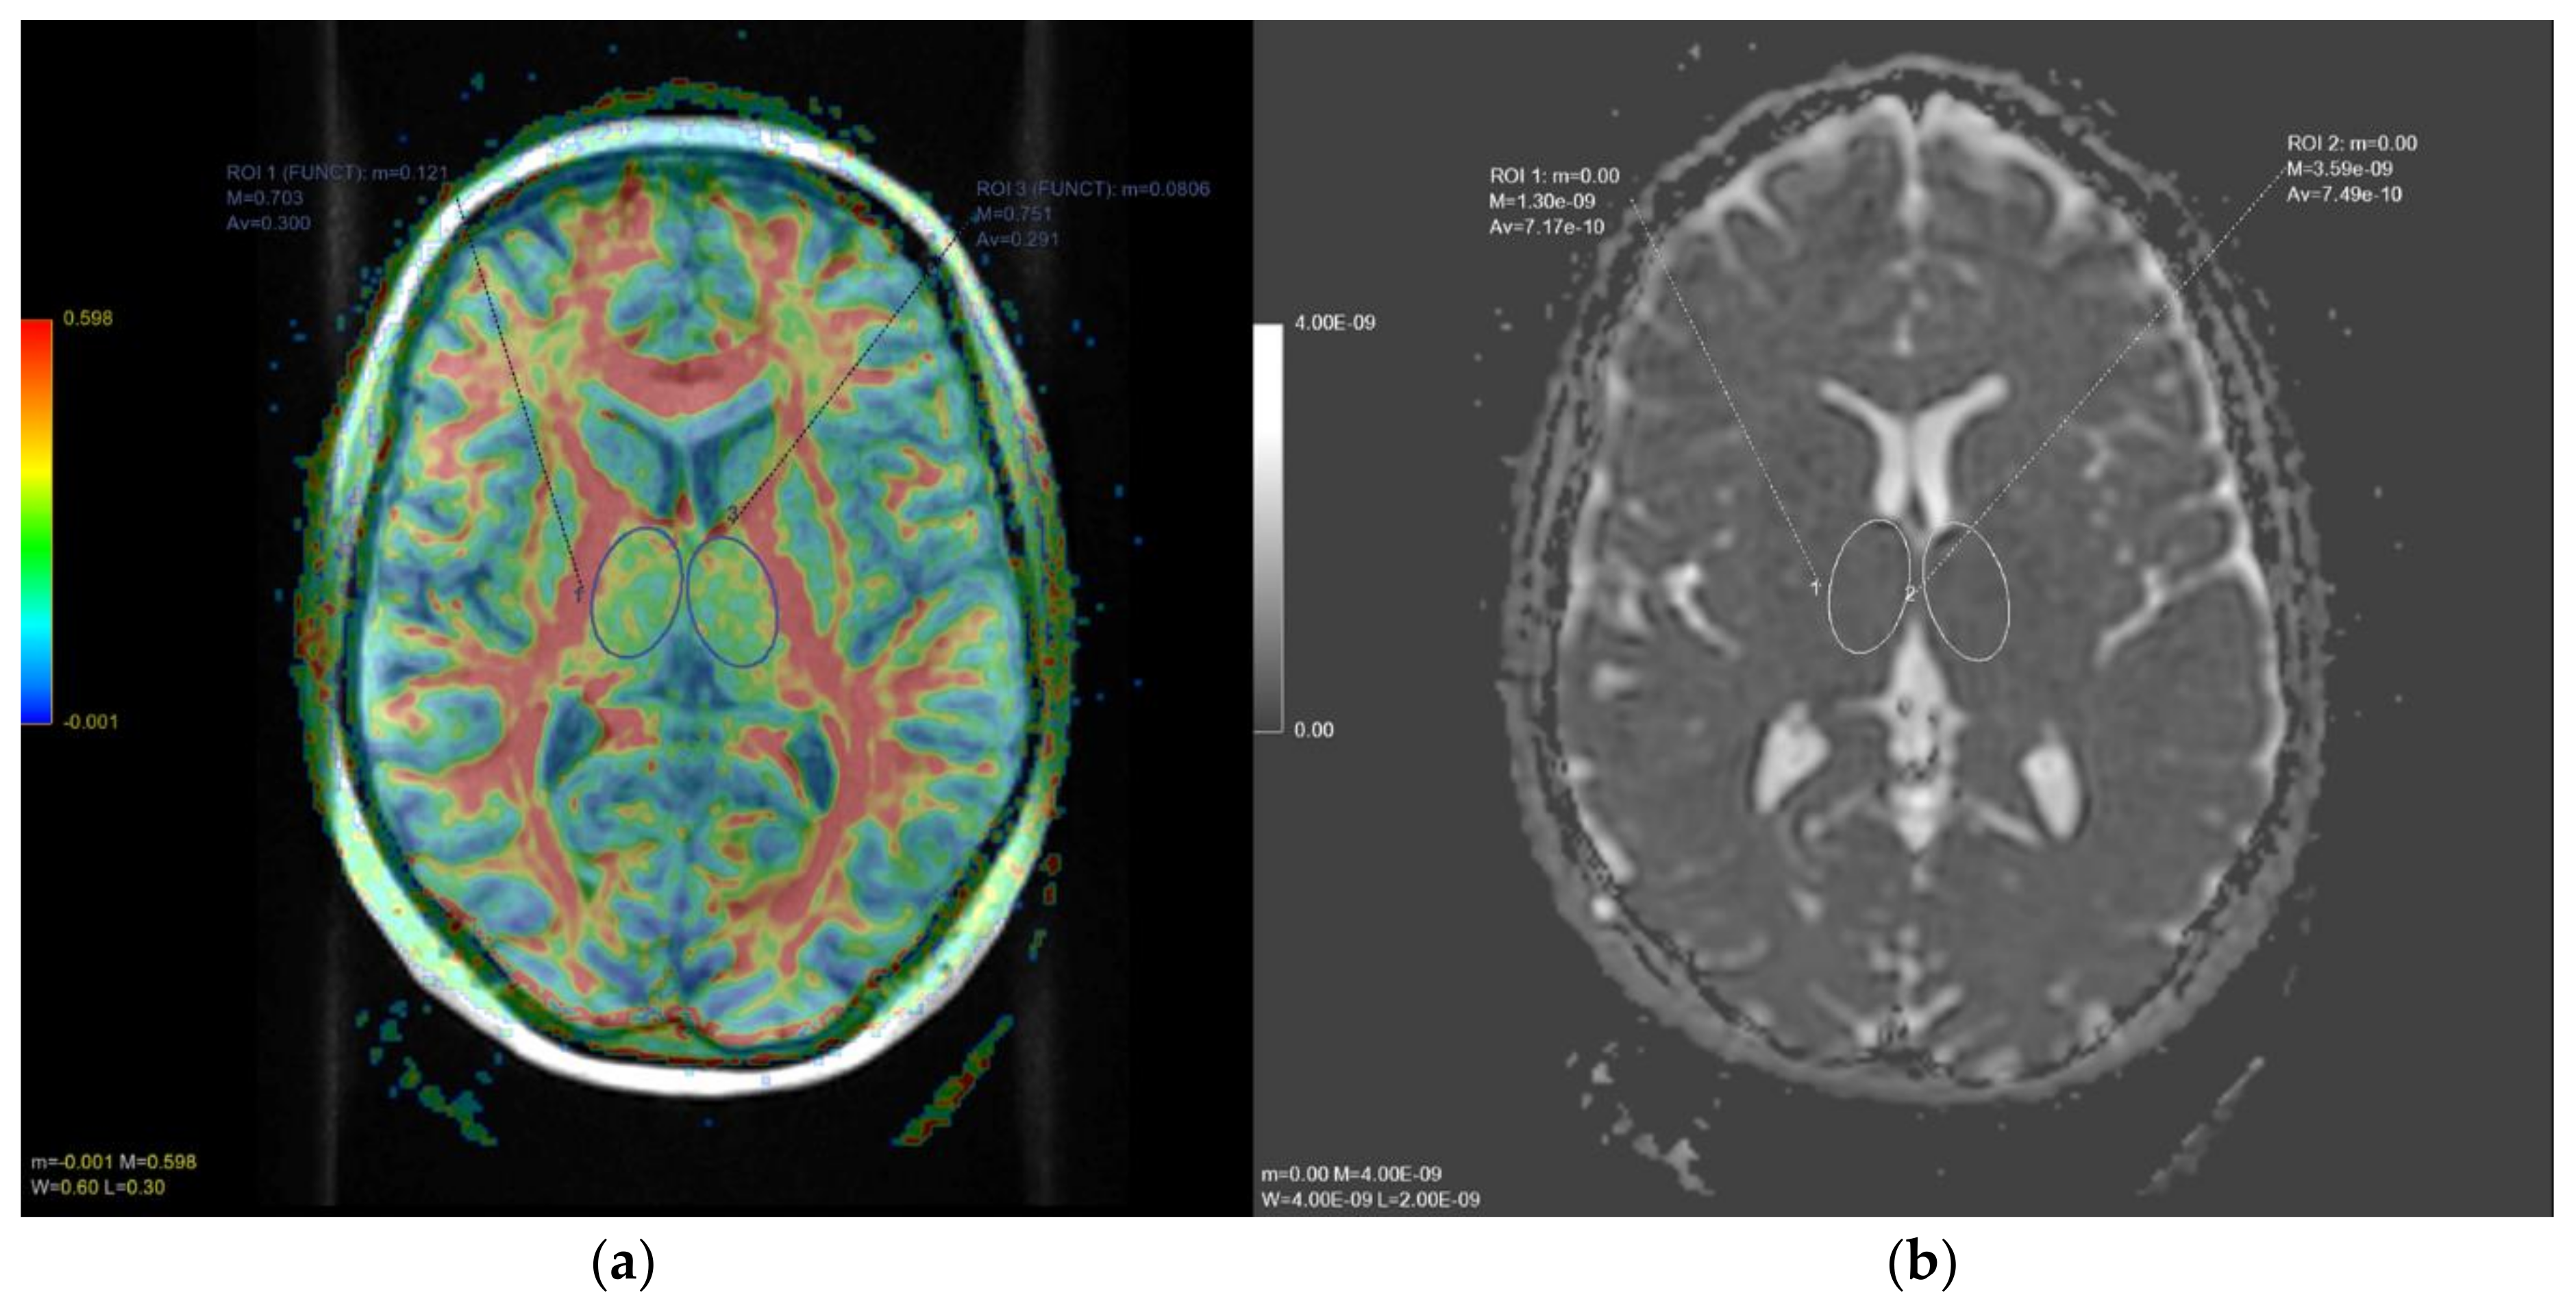

| ADC Dominant Side | ADC Non-Dominant Side | Indexed ADC (Dominant/Non-Dominant Hemisphere) | FA Values Dominant Side | FA Values Non-Dominant Side | Indexed FA (Dominant/Non-Dominant Hemisphere) | |

|---|---|---|---|---|---|---|

| Control Group | 7.33 × 10−6 ± 0.40 | 7.90 × 10−6 ± 0.55 | 0.91 ± 0.10 | 0.36 ± 0.07 | 0.32 ± 0.06 | 1.25 ± 0.14 |

| Study Group | 7.55 × 10−6 ± 0.66 | 7.19 × 10−6 ± 0.51 | 1.04 ± 0.12 | 0.31 ± 0.04 | 0.32 ± 0.04 | 0.98 ± 0.08 |

| p-value | p = 0.11 | p = 0.40 | p = 0.04 | p = 0.10 | p = 0.8 | p = 0.001 |